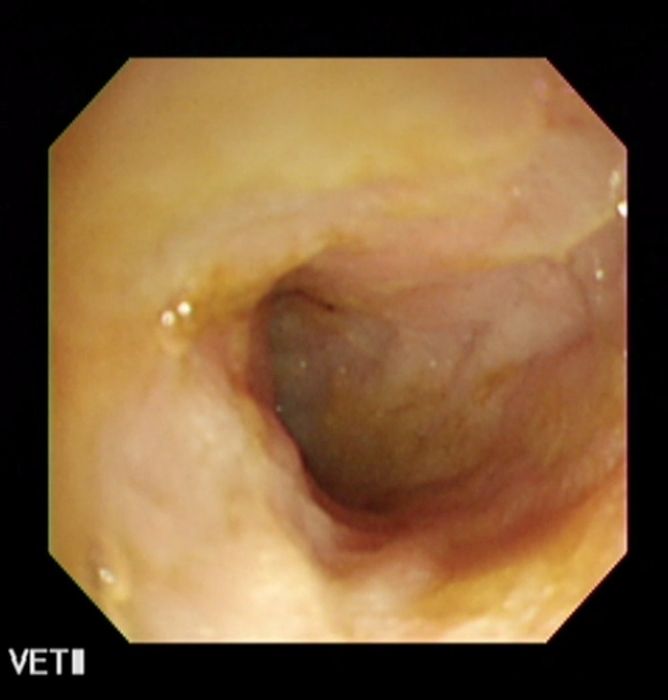

↑内視鏡で見た炎症性腸疾患を起こしている犬の腸内。粘膜がでこぼこしてみえます